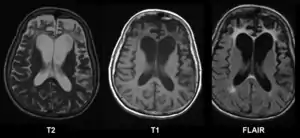

| Brain MRI of a female of 65 years with frontotemporal dementia. Cortical and white matter atrophy of the frontal lobes is clear in all images. | |